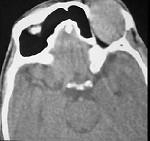

问题 男性45岁,左眼疼痛伴视力下降1个多月,左眼明显外突,CT扫描如图所示,最可能诊断为()

选项 A.左侧眶内炎性假瘤 B.眶内血管瘤 C.眶内纤维瘤 D.眶内结核 E.眶内转移瘤

答案 A